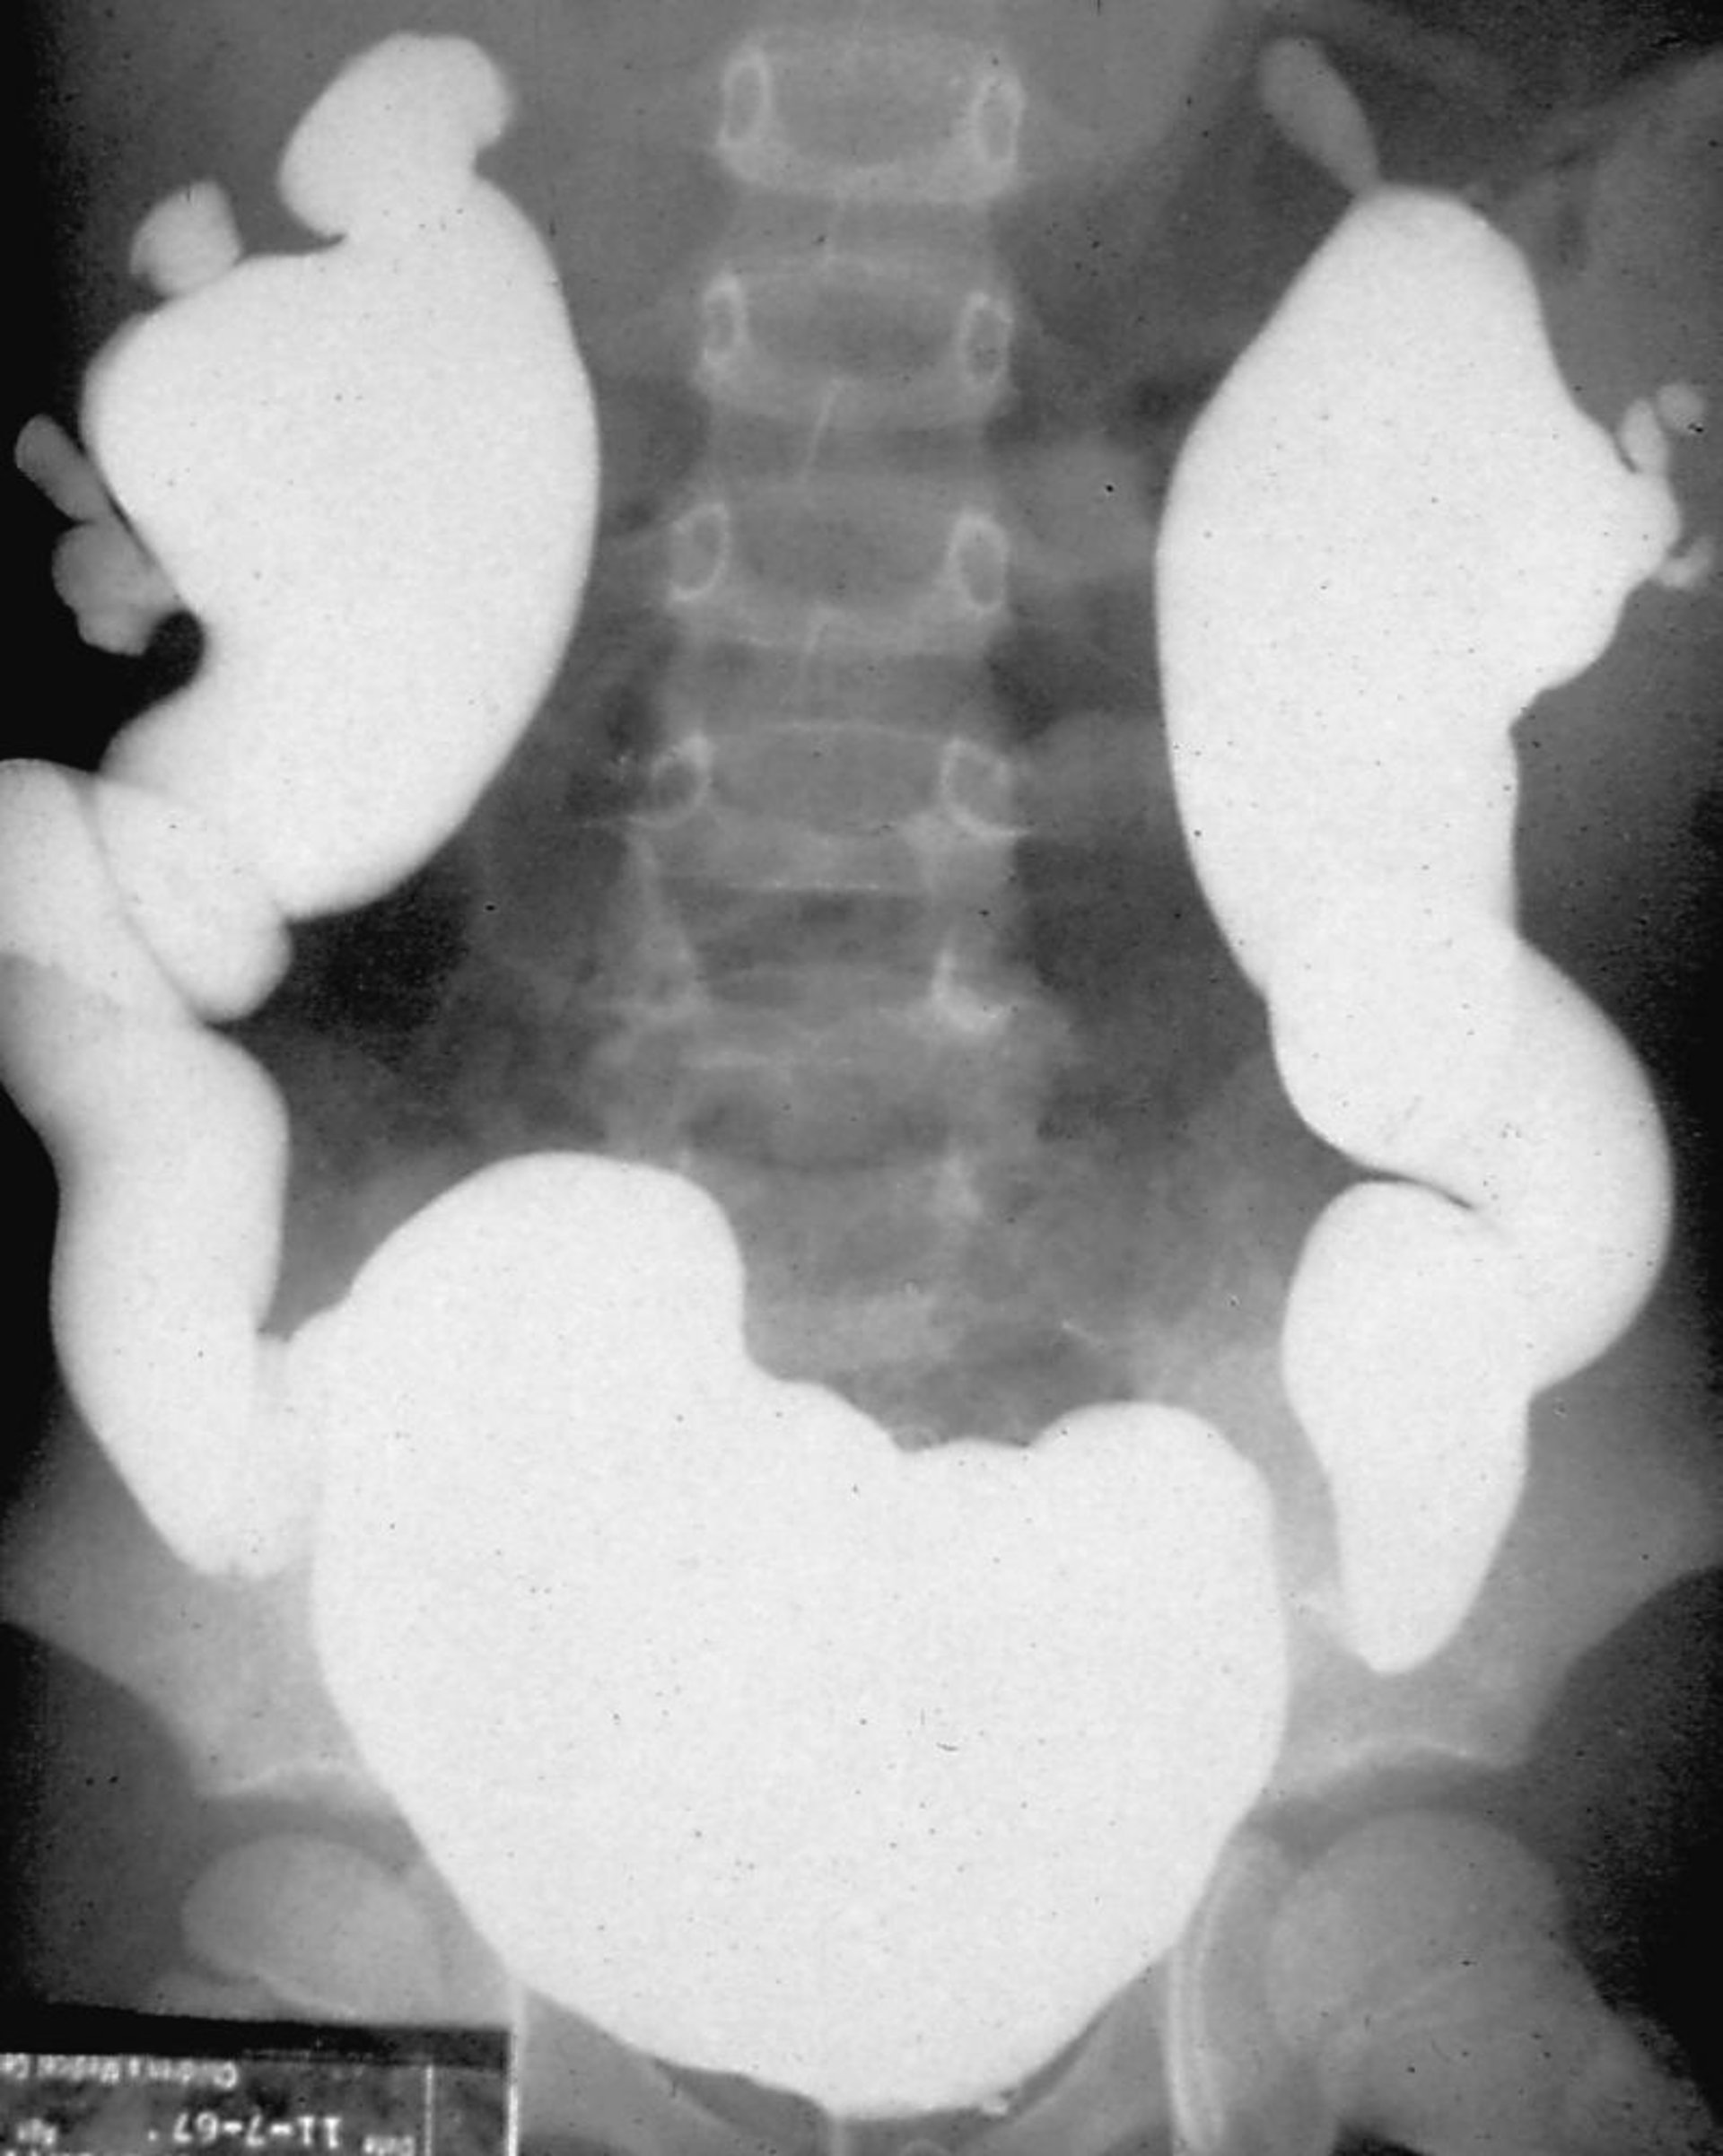

Refluxnephropathie (Miktionszystourethrogramm)

Bei der Miktionszystourethrographie wird die Blase mit Radiokontrastmittel gefüllt und unter Durchleuchtung auf Reflux beobachtet, entweder während der Phase der Blasenfüllung oder während der Miktion.